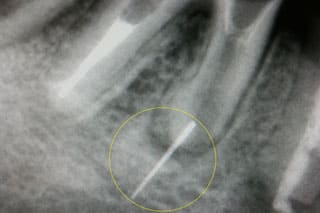

CASE02 根管内異物除去①(リーマ除去)

根管治療は歯科治療の中で最も難しく、奥の深い治療と言っても過言ではありません。 しかしながら健康保険制度により、重要な治療でありながら保険点数が低いため、細かく丁寧に治療をしていない事がレントゲン上でしばしば見受けられます。また非常に細かい作業を要求されるため、根管内を掃除するリーマー(針の様な物)という器具の操作を雑に行うと、根管内で折れこんでしまい、逆に歯の寿命を短くしてしまう事もあります。

当院では他の歯科医院さんで、その様な事になってしまった歯のレスキューを行っております。担当の先生が、リーマーが折れこんでしまった事を患者様にお伝えしていれば良いのですが、多くの場合患者様はその事を伝えられていないケースが多いと感じております。

左側のレントゲン写真はリーマーが折れこみ、骨に刺さり、骨の中で膿の袋を作ってしまっている状態です。他の歯科医院さんから何度行っても摘出が出来なかったとの事で御依頼を頂きました。慎重にその折れこんだリーマーを除去し、根管治療を行い、最終的にMTAセメントという歯を修理するセメントで封鎖しました。